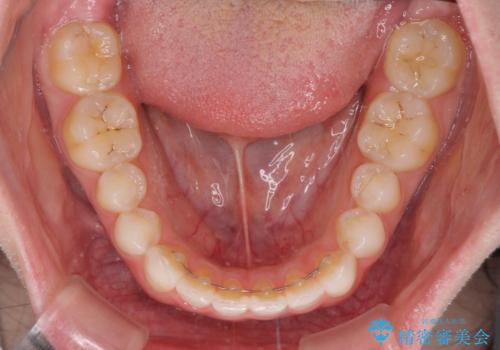

- 前歯の歯並びと虫歯を気にして来院された患者様です。

上下前歯の歯列不正はインビザラインにより歯列を整え、その後に、前歯5本をオールセラミッククラウンにて補綴治療することとしました。

矯正治療前に前歯のむし歯治療を行ったものの、樹脂で充填するには虫歯が広範囲であったため、審美的に問題がありました。